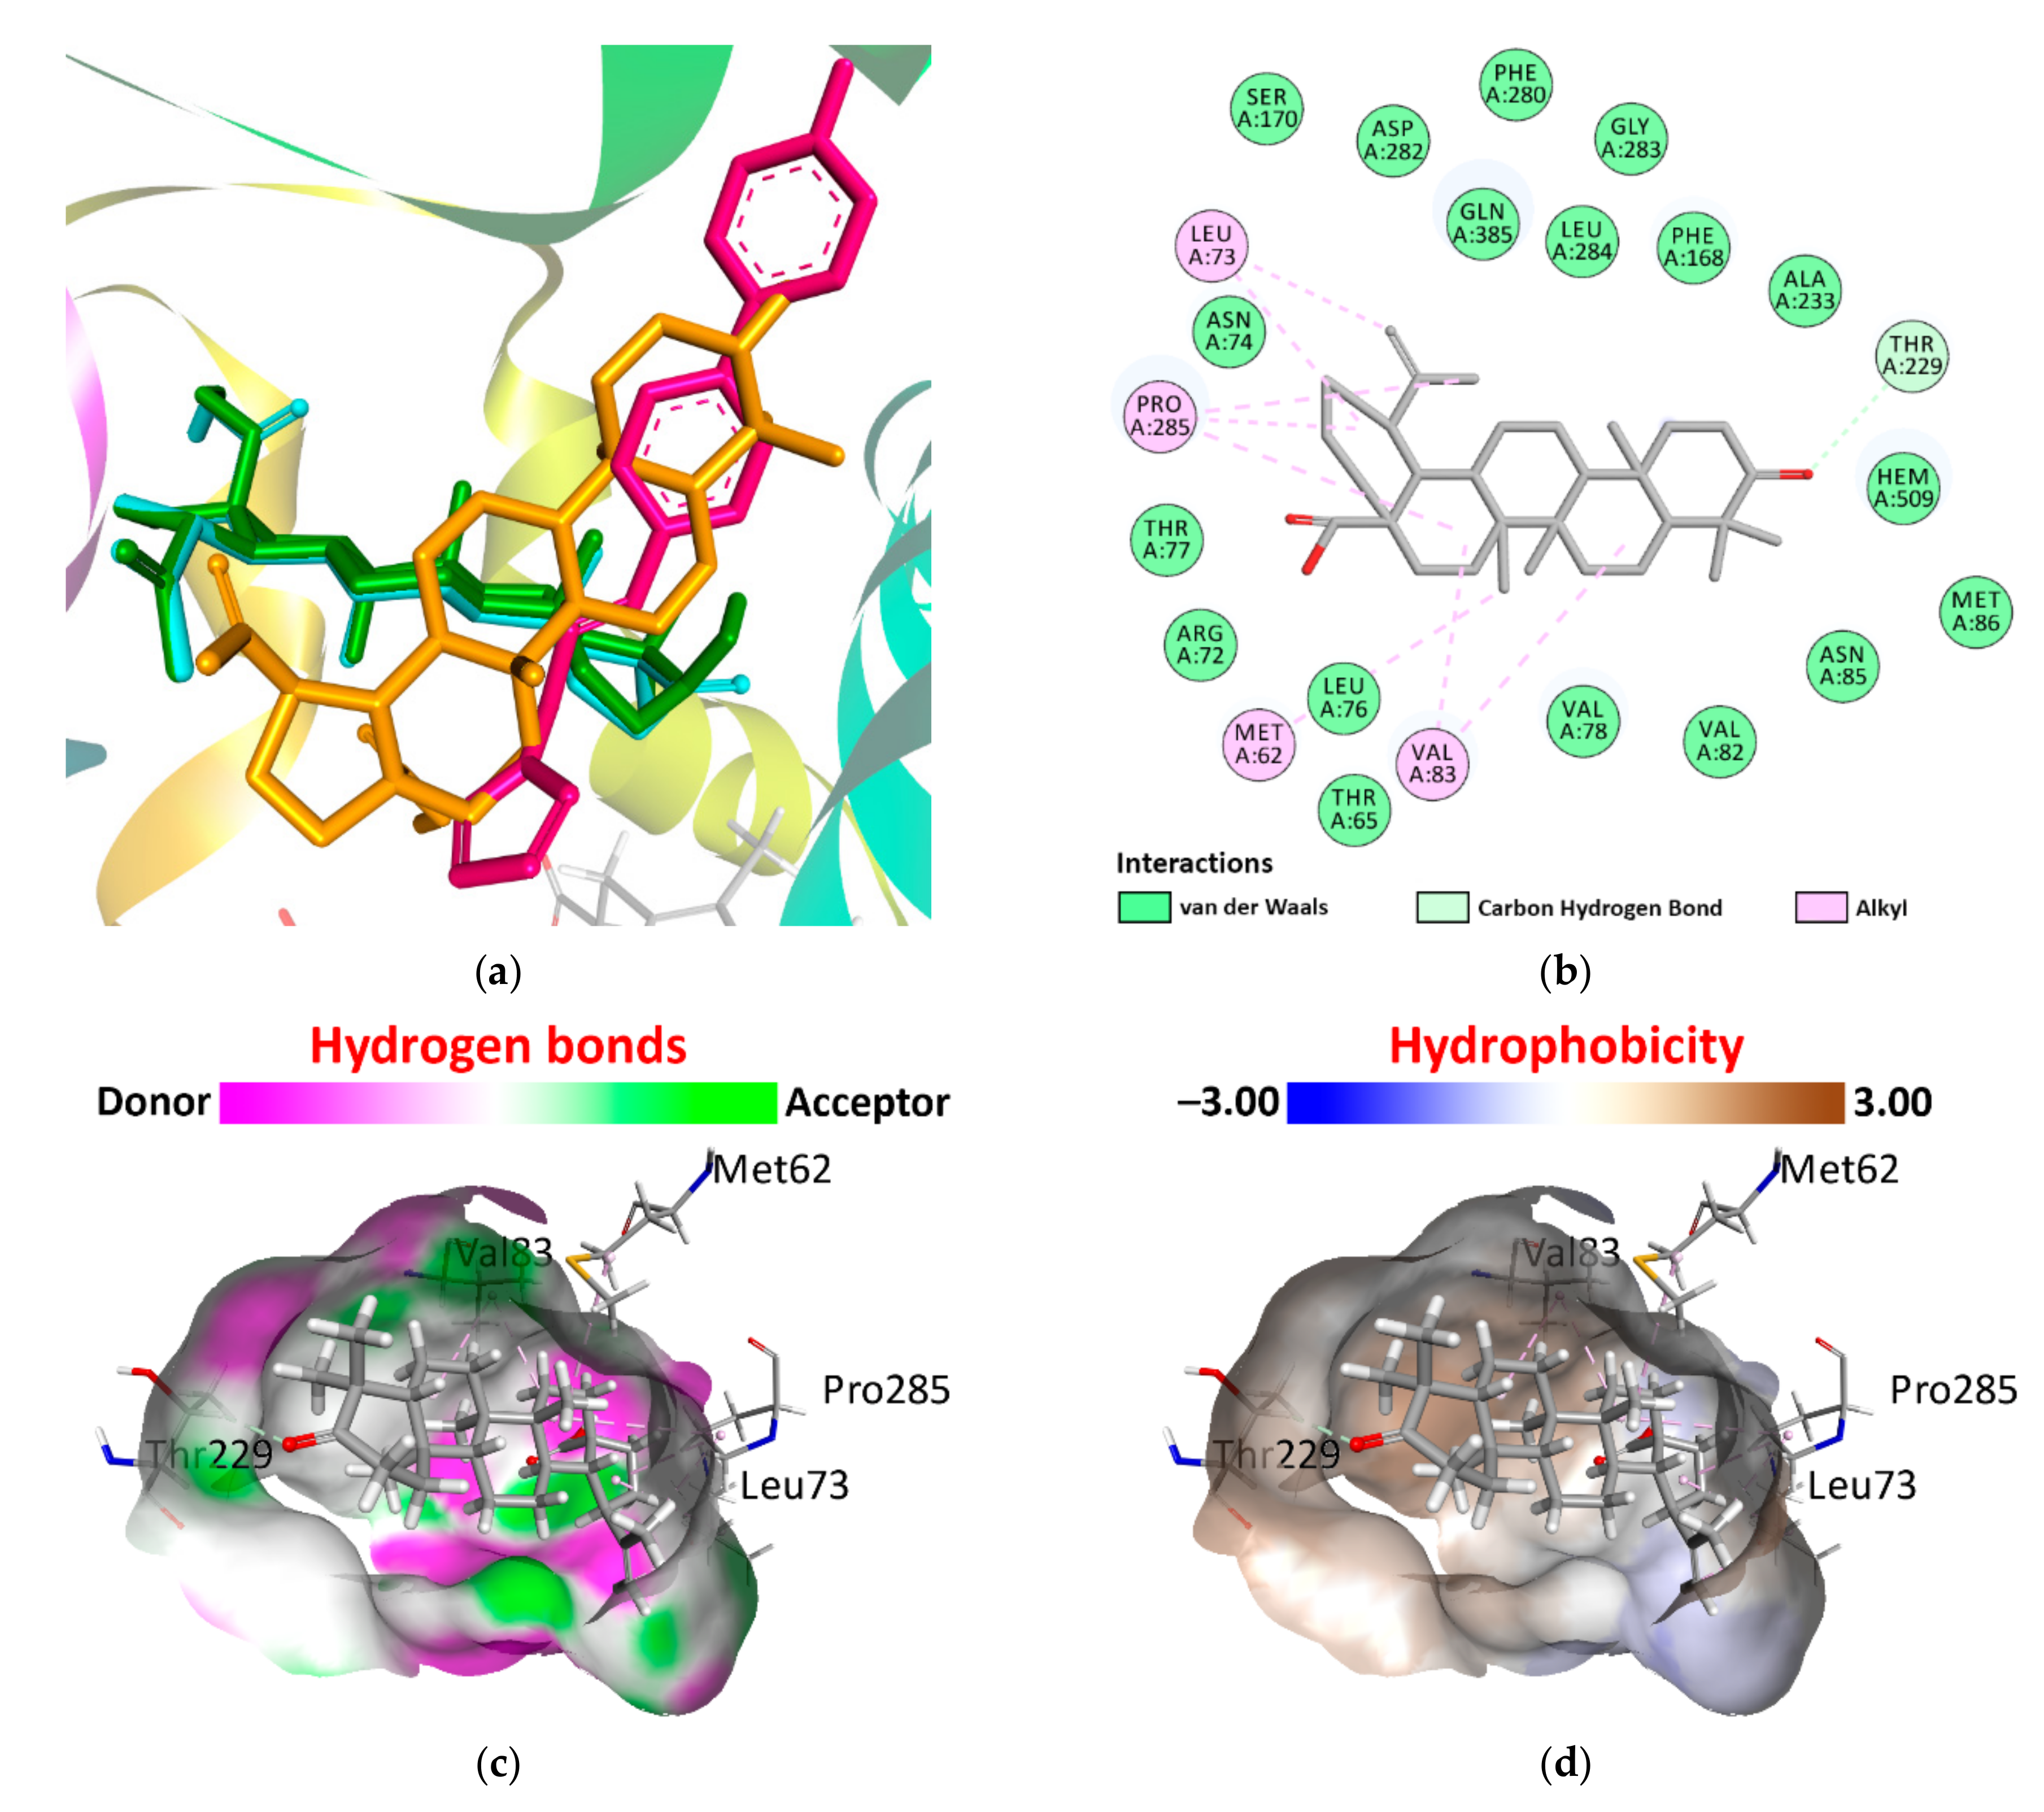

2.1. Pharmacophore Models and Molecular Docking

- Hanwell, M.D.; Curtis, D.E.; Lonie, D.C.; Vandermeersch, T.; Zurek, E.; Hutchison, G.R. Avogadro: An advanced semantic chemical editor, visualization, and analysis platform. J. Cheminform. 2012, 4, 17. [Google Scholar] [CrossRef]

- Berman, H.M.; Westbrook, J.; Feng, Z.; Gilliland, G.; Bhat, T.N.; Weissig, H.; Shindyalov, I.N.; Bourne, P.E. The Protein Data Bank. Nucleic Acids Res. 2000, 28, 235–242. [Google Scholar] [CrossRef]

- BIOVIA; Dassault Systèmes. BIOVIA Discovery Studio, 2020; Dassault Systèmes: San Diego, CA, USA, 2020. [Google Scholar]

- Morris, G.M.; Huey, R.; Lindstrom, W.; Sanner, M.F.; Belew, R.K.; Goodsell, D.S.; Olson, A.J. Autodock4 and AutoDockTools4: Automated docking with selective receptor flexibility. J. Comput. Chem. 2009, 16, 2785–2791. [Google Scholar]

- Trott, O.; Olson, A.J. AutoDock Vina: Improving the speed and accuracy of docking with a new scoring function, efficient optimization, and multithreading. J. Comput. Chem. 2010, 31, 455–461. [Google Scholar] [CrossRef]

- Eberhardt, J.; Santos-Martins, D.; Tillack, A.F.; Forli, S. AutoDock Vina 1.2.0: New Docking Methods, Expanded Force Field, and Python Bindings. J. Chem. Inf. Model. 2021, 61, 3891–3898. [Google Scholar] [CrossRef]

| Mtb CYP121 | 6TET | N5Z | −9.80 | 7.14 |

| Betulin | −9.79 | 7.13 | ||

| Betulonic acid | −11.02 | 8.03 | ||

| Betulinic acid | −9.52 | 6.94 | ||